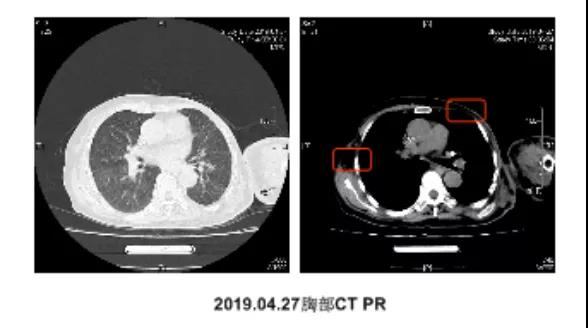

●2周期、4周期后CT疗效评估:均为PR

●6周期后CT疗效评估:SD